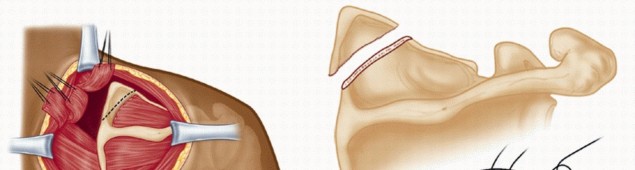

TECH FIG 1 • (continued) D,E. Resection of the superomedial border of the scapula. F. The detached muscles are reattached to the scapula through drill holes. G. The final repair of the detached levator scapulae and rhomboids. 1. ## Arthroscopic Bursectomy

TECH FIG 1 • (continued) D,E. Resection of the superomedial border of the scapula. F. The detached muscles are reattached to the scapula through drill holes. G. The final repair of the detached levator scapulae and rhomboids. 1. ## Arthroscopic Bursectomy